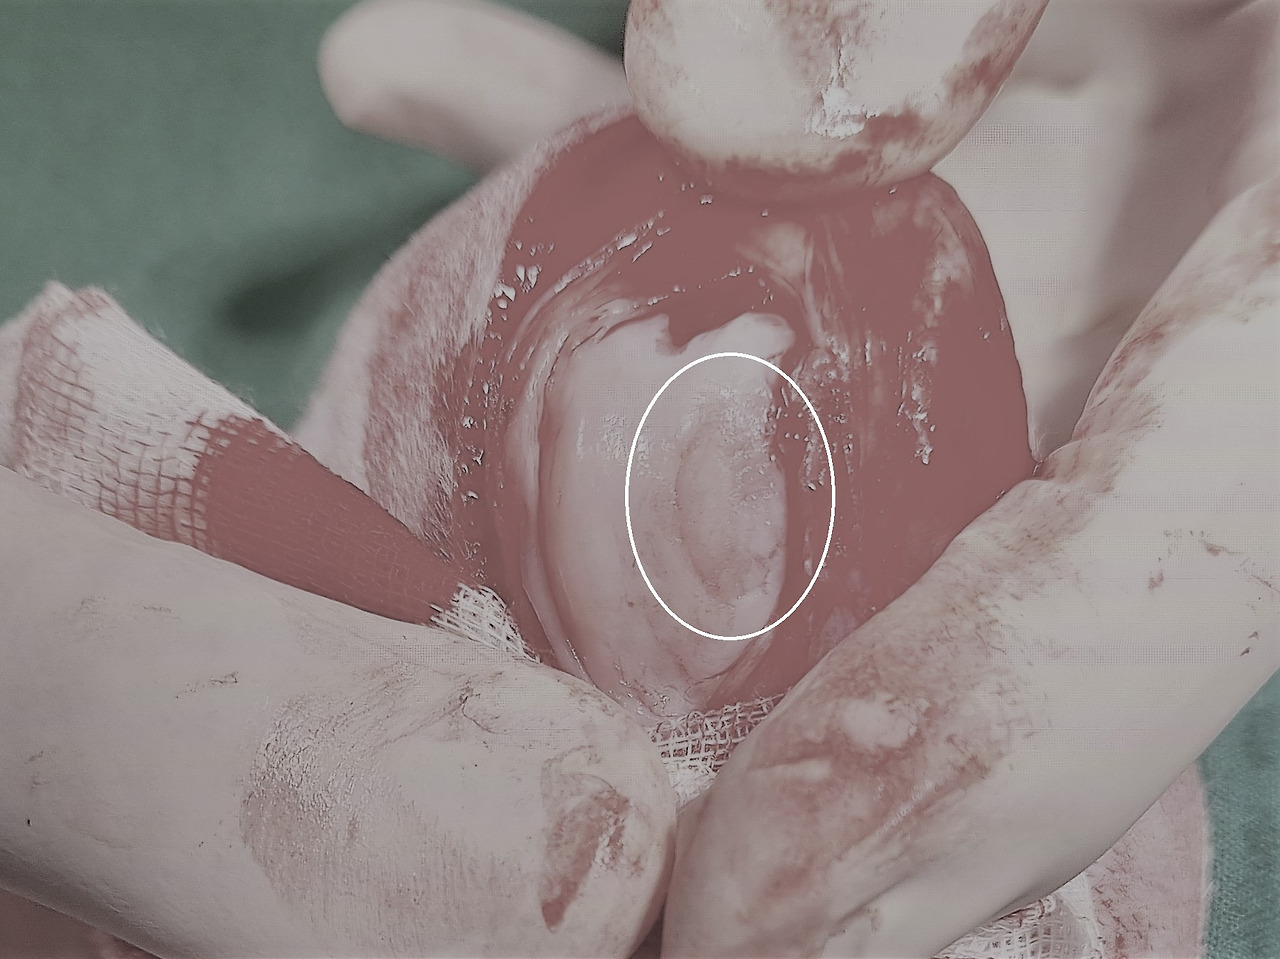

슬개골 탈구-1.jpg 슬개골 탈구로 닳은 관절면

이 사진은 4단계 슬개골 탈구로 수술을 받은 아이의 관절면 모습이에요. 하얀 원 안의 닳은 상처가 보이시나요? '슬개골 탈구'는 '슬개골'이라는 뼈가 비정상적인 경로로 이동을 하여 원래 위치에서 '탈구'되는 것을 의미해요. 그런데 탈구가 될 때 허벅지 뼈에 있는 작은 언덕(활차구 능선; Trochlear ridge)을 하나 넘어가게 되고 이로 인해 뼈에 비정상적인 마찰이 발생해요.

많이 걸으면 걸을수록, 슬개골 탈구가 심하면 심할수록 이곳의 마찰 역시 심해지게 되고 이로 인해 뼈가 긁히고 관절 내부에 염증이 생겨나요. 이렇게 시작된 관절의 염증은 퇴행성 관절염으로 발전하여 무릎 관절 내부의 모든 구조물에 퇴행성 변화를 일으켜요. 뿐만 아니라 십자인대가 끊어질 확률도 높아지게 돼요.